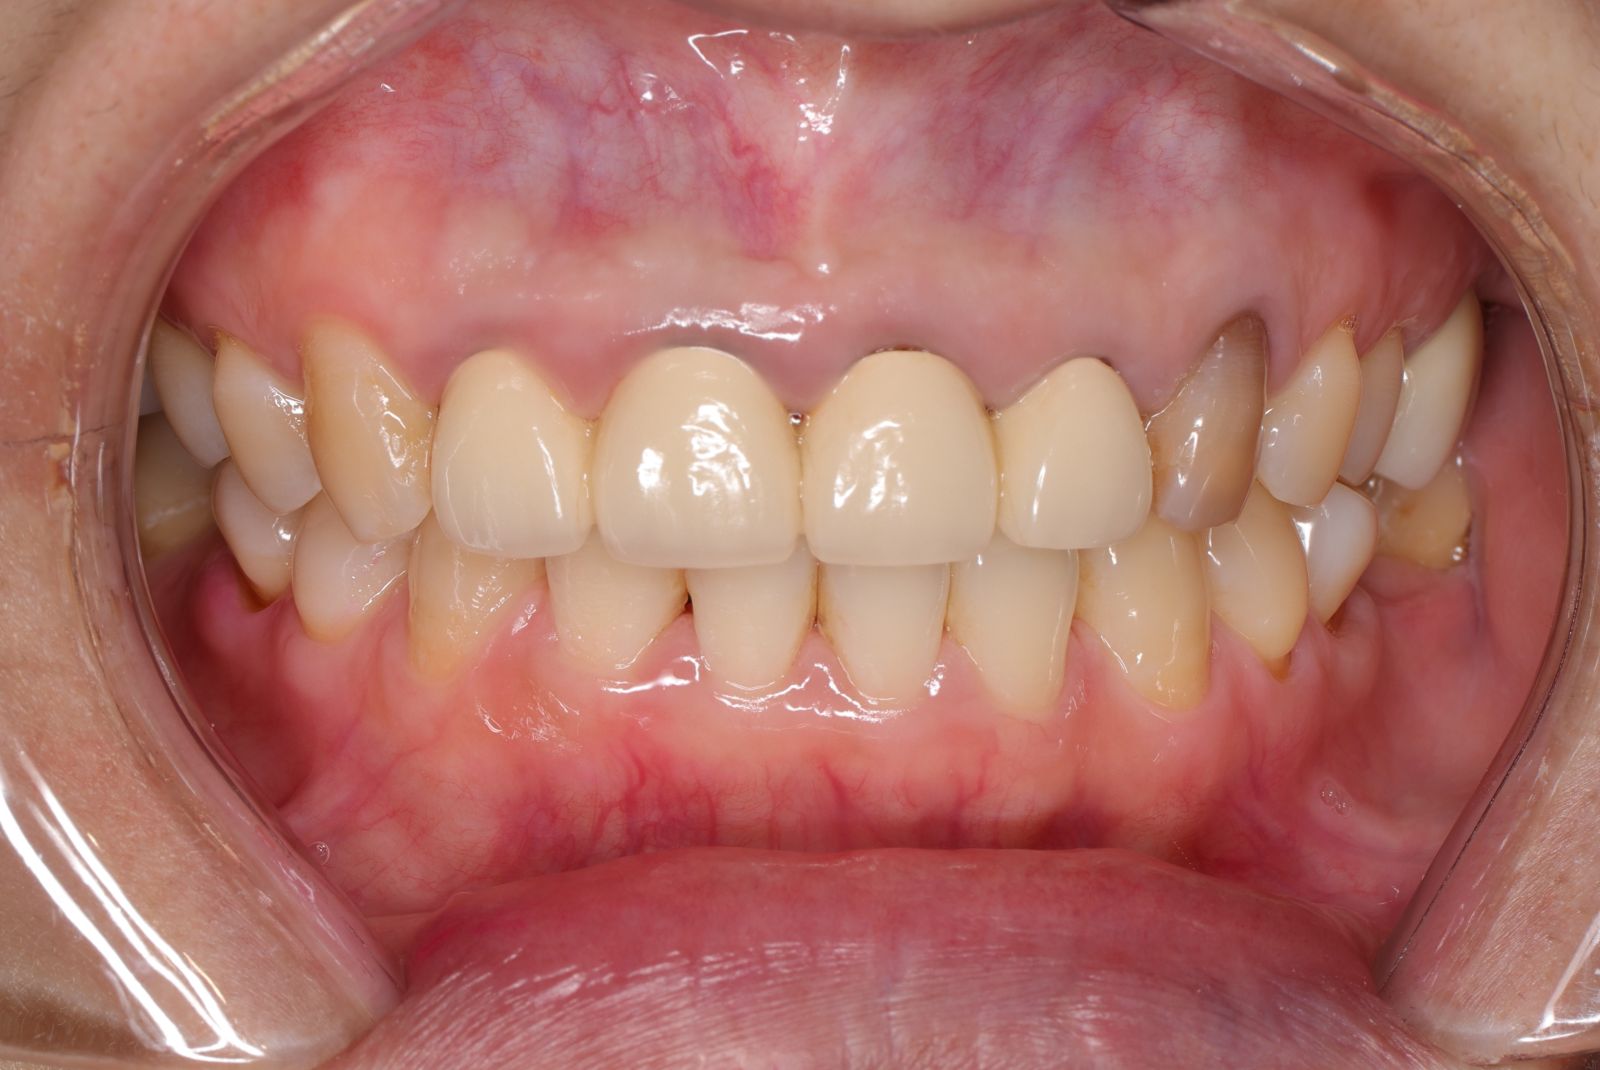

【 案 例 一 】

- 患者因為以前矯正疏於清潔,很多的蛀牙以及抽過神經的牙齒斷裂缺損,脆弱的牙齒影響健康及美觀。把牙齒磨小的過程會挖除蛀牙,保留健康的牙齒,用陶瓷纖維牙釘維持強度,過程會先用臨時牙套與醫師討論型態,最後依照自己喜歡的顏色及外型設計專屬於自己的前牙美學全瓷冠假牙!